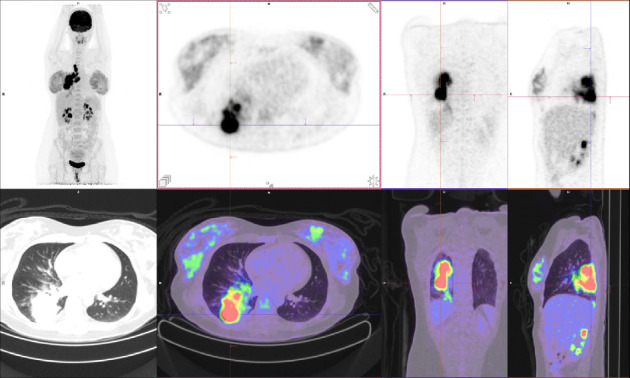

由于靶向治疗的安全性数据有限,妊娠期间癌基因驱动的非小细胞肺癌(NSCLC)的管理面临着独特的挑战。间变性淋巴瘤激酶(ALK)重排非小细胞肺癌是一种罕见的疾病,但越来越多的人认识到它存在于年轻女性中,包括怀孕期间。在这里,我们报告一例37岁的女性在她的第一次怀孕期间被诊断为转移性alk重排NSCLC,她开始使用alectiinib。在此之后,她成功地进行了第二次怀孕,同时接受了alectinib治疗(在妊娠6-10周期间暂停,以避免器官发生的关键时期)。两次怀孕都产生了健康的婴儿,没有并发症或发育迟缓的迹象。本病例强调了多学科方法的重要性,包括肿瘤学、母胎医学、临床遗传学、产科医学和产科,以平衡孕产妇癌症控制和胎儿健康。虽然临床前研究表明阿勒替尼有致畸风险,但这一病例和其他报道的病例表明,在仔细计划的情况下,妊娠期间使用阿勒替尼是安全的。本例胎盘病理检查未发现恶性细胞,母体疾病得到控制。随着靶向治疗延长晚期非小细胞肺癌的生存期,更多的患者可能会考虑怀孕,这强调了需要强有力的证据来指导治疗决策。该病例提供了越来越多的证据,支持alk重排NSCLC患者使用alectinib等靶向治疗来管理妊娠的可行性,同时强调了对暴露后代进行长期随访的重要性。

The management of oncogene-driven non-small cell lung cancer (NSCLC) during pregnancy presents unique challenges due to limited safety data on targeted therapies. Anaplastic lymphoma kinase (ALK)-rearranged NSCLC is a rare but increasingly recognized entity in young women, including during pregnancy. Here, we report the case of a 37-year-old woman diagnosed with metastatic ALK-rearranged NSCLC during her first pregnancy, who was commenced on alectinib. Following this, she had a successful second pregnancy whilst being treated with alectinib (withheld during weeks 6-10 of gestation to avoid the critical period of organogenesis). Both pregnancies resulted in healthy infants with no complications or evidence of developmental delays. This case highlights the importance of a multidisciplinary approach involving oncology, maternal-fetal medicine, clinical genetics, obstetrics medicine, and obstetrics to balance maternal cancer control and fetal health. While preclinical studies of alectinib suggest teratogenic risks, this and other reported cases demonstrate its potential for safe use during pregnancy with careful planning. Pathological examination of the placenta in our case revealed no malignant cells, and maternal disease remained controlled. As targeted therapies extend survival in advanced NSCLC, more patients may contemplate pregnancy, emphasizing the need for robust evidence to guide treatment decisions. This case contributes to the growing body of evidence supporting the feasibility of managing pregnancy in patients with ALK-rearranged NSCLC using targeted therapies like alectinib, while underscoring the importance of long-term follow-up for the exposed offspring.